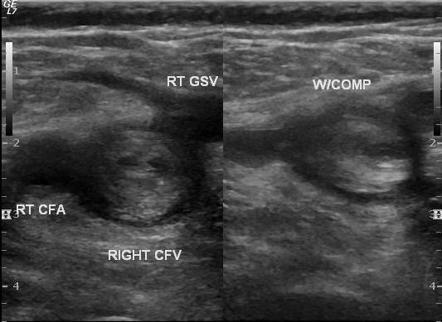

Ultrasound and Doppler Imaging for accurate diagnosis